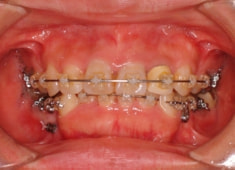

治療法:フルパッシブブラケット:クリアスナップ

治療開始から1年8ヶ月後